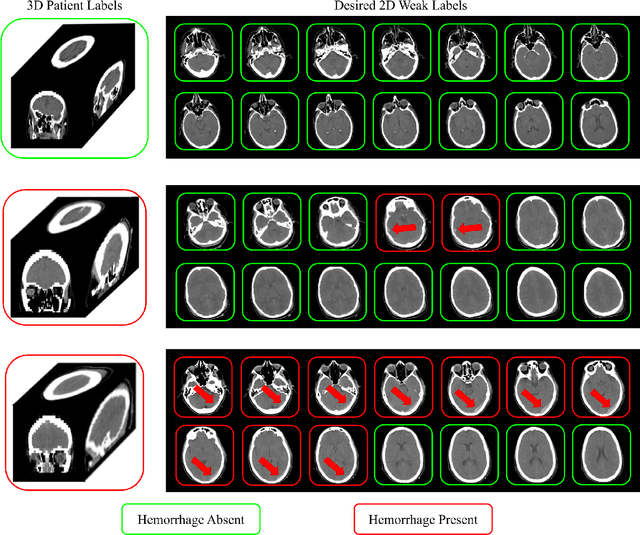

Abstract:Multiple instance learning (MIL) is a supervised learning methodology that aims to allow models to learn instance class labels from bag class labels, where a bag is defined to contain multiple instances. MIL is gaining traction for learning from weak labels but has not been widely applied to 3D medical imaging. MIL is well-suited to clinical CT acquisitions since (1) the highly anisotropic voxels hinder application of traditional 3D networks and (2) patch-based networks have limited ability to learn whole volume labels. In this work, we apply MIL with a deep convolutional neural network to identify whether clinical CT head image volumes possess one or more large hemorrhages (> 20cm$^3$), resulting in a learned 2D model without the need for 2D slice annotations. Individual image volumes are considered separate bags, and the slices in each volume are instances. Such a framework sets the stage for incorporating information obtained in clinical reports to help train a 2D segmentation approach. Within this context, we evaluate the data requirements to enable generalization of MIL by varying the amount of training data. Our results show that a training size of at least 400 patient image volumes was needed to achieve accurate per-slice hemorrhage detection. Over a five-fold cross-validation, the leading model, which made use of the maximum number of training volumes, had an average true positive rate of 98.10%, an average true negative rate of 99.36%, and an average precision of 0.9698. The models have been made available along with source code to enabled continued exploration and adaption of MIL in CT neuroimaging.